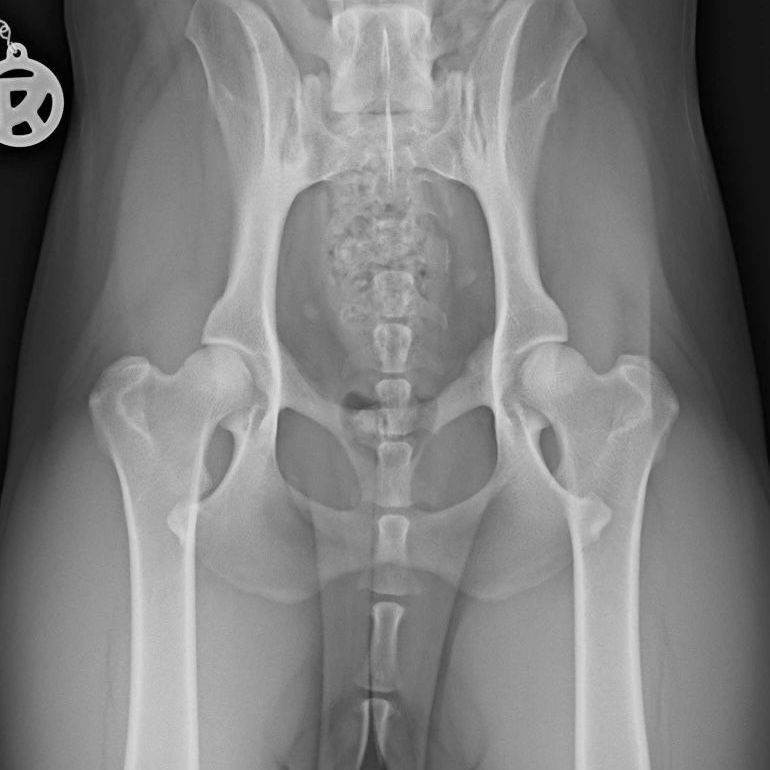

Die Hüftgelenksdysplasie (HD) ist eine multifaktorielle Erkrankung, die häufig bei Haushunden vorkommt und eine Fehlentwicklung des Hüftgelenks zur Folge hat. Neben der haltungs- und ernährungsbedingten Komponente, trägt vor allem auch eine genetische Komponente zu ihrer Entstehung bei.

Entgegen der landläufigen Meinung eine HD könnte erst im Alter von 12 Monaten zuverlässig diagnostiziert werden, kann man Veränderungen im Hüftgelenk schon ab einem Alter von 16 Wochen über ein spezielles röntgendiagnostisches Verfahren (PennHIP) zuverlässig feststellen. Gerade bei Hündinnen, die später zur Zucht zugelassen werden sollen, wäre dies Verfahren anzuraten, da dieses genauere Aussagen über die Gesundheit der Hüfte zulässt, als das herkömmliche Röntgenverfahren.